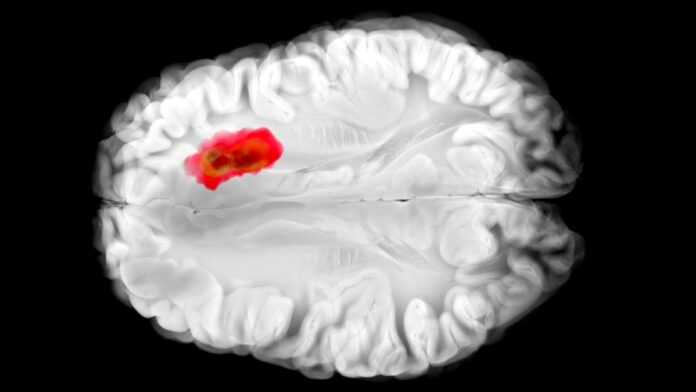

Було показано, що препарат гідралазин, який десятиліттями використовувався для лікування високого кров’яного тиску, пригнічує ключовий фермент, пов’язаний з агресивною гліобластомою, однією з найнебезпечніших форм раку мозку. Відкриття, зроблене дослідниками з Університету Пенсільванії, проливає світло на механізм дії препарату і відкриває двері для нових методів лікування раку.

Протягом багатьох років механізм дії гідралазину залишався неясним. Тепер вчені знають, що він блокує 2-аміноетантіолдіоксигеназу (ADO), фермент, який пухлини використовують для більш ефективного поширення. ADO діє як «сигнал тривоги»: коли рівень кисню падає, він запускає реакцію, яка звужує кровоносні судини, руйнуючи білки RGS. Пухлини гліобластоми розвиваються завдяки цьому процесу, виробляючи хімічну речовину під назвою гіпотаурин, яка допомагає їм виживати та протистояти лікуванню.

Це важливо, оскільки раніше не було відомих інгібіторів ADO. Здатність гідралазину пригнічувати ADO in vitro призупинила ріст гліобластоми, що вказує на потенційний новий спосіб контролю поширення раку.